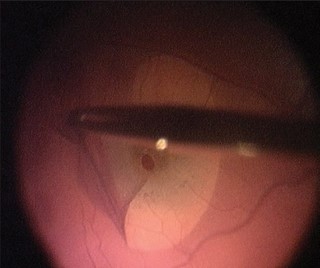

O tratamento é cirúrgico com cirurgia de vitrectomia e remoção da membrana com uma pinça especial de retina.